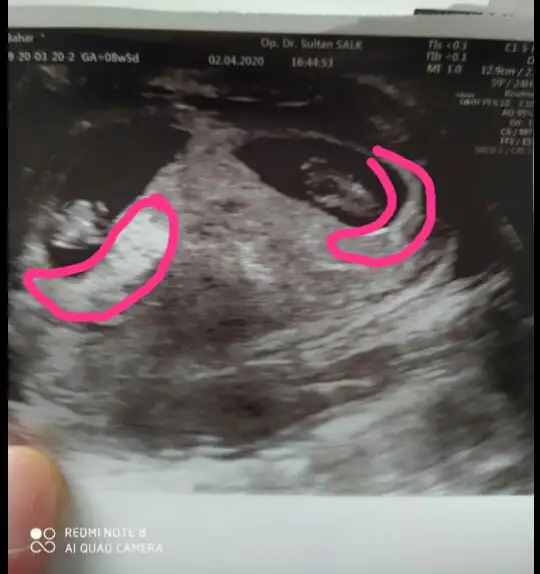

Banada bakarmısınız kız mı erkek mi 🙏

Eklentiler

• AE59961B-285A-4800-BE53-1997DF2112F0.webp

AE59961B-285A-4800-BE53-1997DF2112F0.webp

17,4 KB · Görüntüleme: 112

• 6A55CC0C-EF50-4D7B-953A-A2C9DC7AE417.webp

6A55CC0C-EF50-4D7B-953A-A2C9DC7AE417.webp

45 KB · Görüntüleme: 96

• 97C90445-9609-4D20-A2BA-3AAF46D17AF2.webp

97C90445-9609-4D20-A2BA-3AAF46D17AF2.webp

29 KB · Görüntüleme: 108

• 4C86B8AF-00EB-41F4-873B-D8D70E3B5095.webp

4C86B8AF-00EB-41F4-873B-D8D70E3B5095.webp

26,8 KB · Görüntüleme: 110

• AD6DA00C-B8C6-45E1-8BDA-DBCE9775C0C1.webp

AD6DA00C-B8C6-45E1-8BDA-DBCE9775C0C1.webp

19,6 KB · Görüntüleme: 108